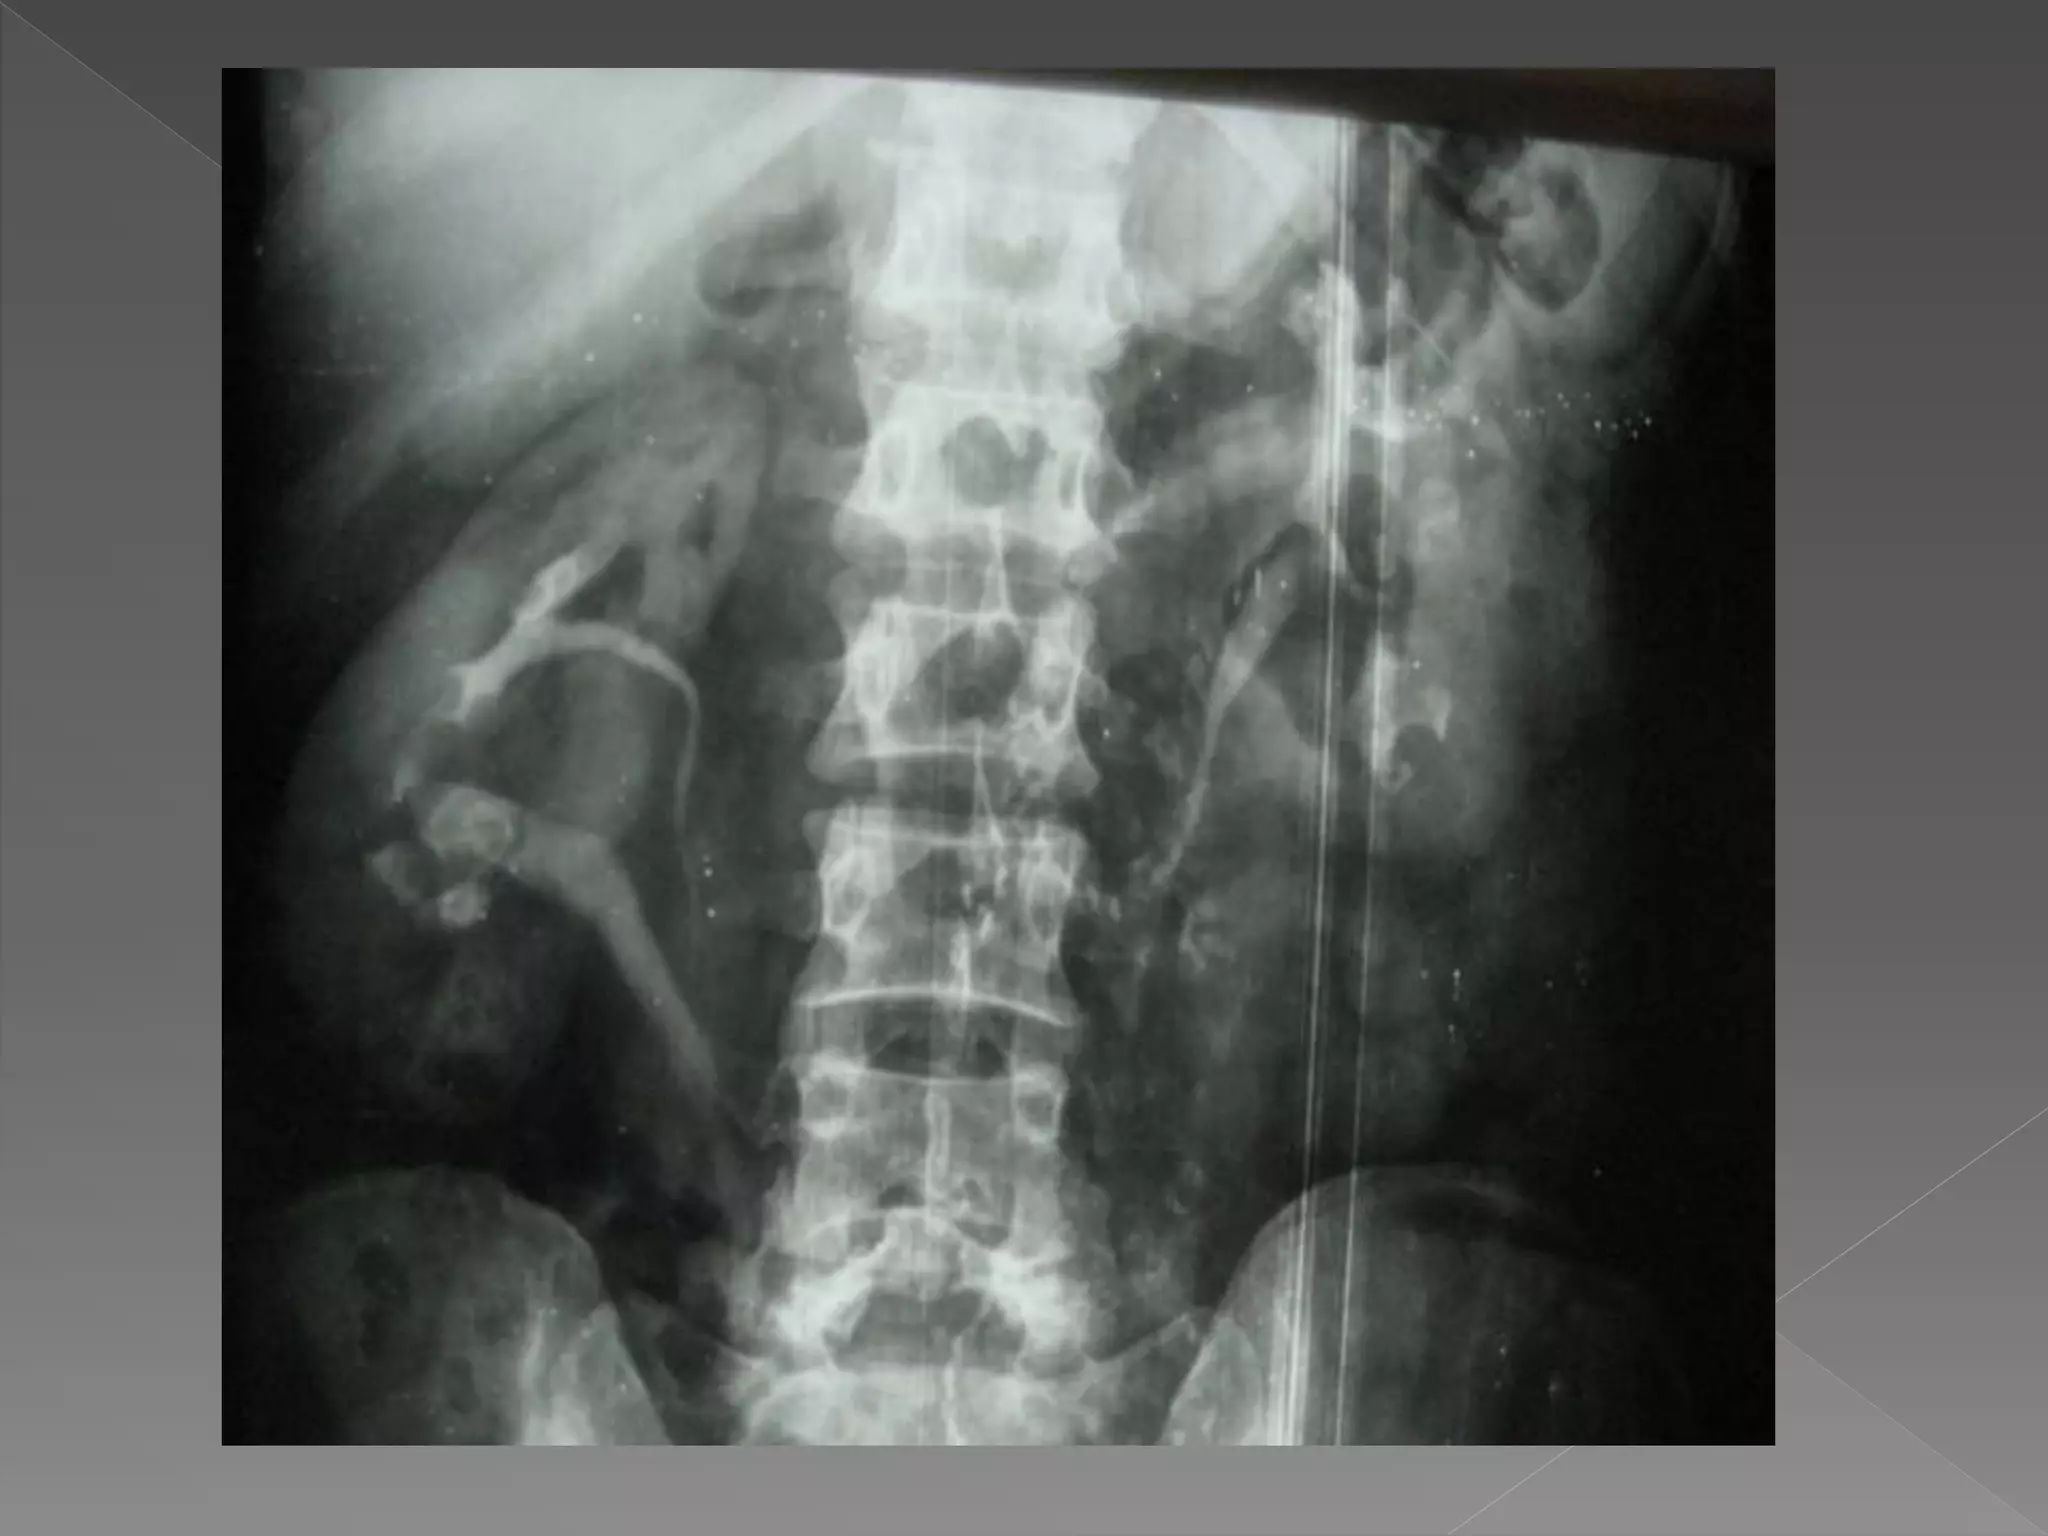

 Acute Obstruction:

 There is delay in opacification of the

collecting system.

 Delay may be considerable up to 24 hrs

or more.

 It is then necessary to perform additional

films

 Time interval b/w films is doubled

0.5 hrs/ 1 hr/ 2 hrs/ 4 hrs/ 16 hrs/ 24 hrs

as necessary.